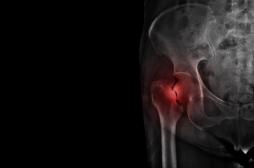

J'AI MAL

J ai Mal Bras et mains Bras et mains Tête et cou Torse et haut du dos Jambes et pied